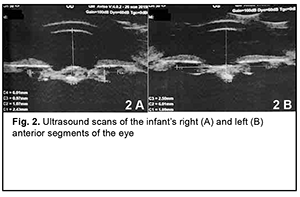

The secondary diagnosis was residual effects of congenital intrauterine infection, impaired cerebrospinal fluid dynamics, severely delayed statokinetic and psychoemotional development, functional fetal communications, open oval windows and CNS lesion due to intrauterine hypoxia. Findings from the history: The child was born at term (at 39 weeks of gestation) with a birth weight of 2890 g by a young healthy mother after her first planned pregnancy, and had no significant family history. Visual acuity was light perception OU. Examination under anesthesia: Intraocular pressure (IOP) was 27.0 mmHg OD and 25.0 mmHg OS. Keratometry was 43.0 D OD and 44.5 D OS. A-scan ultrasound biometry showed an axial length of 15.74 mm, an anterior chamber depth of 2.4 mm, and a lens thickness of 1.3 mm OD. The patient's left eye had an axial eye length of 14.68 mm, an anterior chamber depth of 1.6 mm, and a lens thickness of 1.9 mm. A-scan ultrasound of the right eye showed an anterior chamber depth of 2.4 mm and the non-homogeneous lens looking like a membrane which was thickened at the center and beneath the iris (Fig. 2 A). In addition, it showed a lens thickness of 1.1 mm and a lens horizontal diameter of 6.0 mm. The vitreous exhibited individual punctal-and-fibrous structures of low echogenicity. The retina appeared attached. Temporally to the optic disc, there was excavation of the vitreoretinal contour (excavation depth, 0.5 mm; excavation length, 6.0 mm), a posterior staphyloma.

A-scan ultrasound of the left eye showed an anterior chamber depth of 2.5 mm and the non-homogeneous lens looking like a membrane which was thickened at the center and beneath the iris. In addition, it showed a lens thickness of 1.1 mm and a lens horizontal diameter of 6.0 mm (Fig. 2 B). The vitreous exhibited individual punctal-and-fibrous structures of low echogenicity. The retina appeared attached. Temporally to the optic disc, there was excavation of the vitreoretinal contour (excavation depth, 0.4 mm; excavation length, 5.5 mm), a posterior staphyloma. TORCH infection enzyme immunoassays: The child was found to be infected with cytomegalovirus (IgG antibodies, 11.5 IU/ml), herpes simplex virus 1/2 (IgG antibodies, 8.74 IU/ml), and Epstein-Barr virus (EBV capsid IgG antibodies, 18.92 IU/ml; EBV nuclear IgG antibodies, 17.74 IU/ml), whereas the mother, with cytomegalovirus (IgG antibodies, 34.1 IU/ml) and herpes simplex virus 1/2 (IgG antibodies, 46.7 IU/ml). Given the physical findings and general state of the child, the first treatment stage included anti-inflammatory and antibacterial therapy as follows: bilateral eye drops of okomistyn, four times daily; azopt, twice daily; maxitrol, four times daily; 0.15 ml parabulbar dexamethasone injection, №4. In addition, the infant was given 1.5-ml cefix, once daily orally, and laktiale, one sachet daily, for five days. The infant was seen and treated by the neonatologist, infection specialist and neurologist at the place of residence. Given low titers of IgG antibodies specific for herpes viruses (cytomegalovirus, herpes simplex virus 1/2, and Epstein-Barr virus), and the absence of clinical manifestations of infection, the infection specialist believed there was no need for specific antiviral therapy. Three months later, the infant’s general state improved, and he underwent re-examination under anesthesia. The clinical condition of the eyes improved. In addition, there was no change in visual acuity. The IOP decreased to 15.0 mmHg OD and 17.0 mmHg OS. The axial length as assessed by ultrasound A-scan biometry improved to 16.26 mm OD and 15.72 mm OD. Ultrasound scanning of both eyes showed the same changes as previously. Given that there was no vision in both eyes, on June 11, 2020, the right eye underwent surgery which included synechiotomy and lensectomy of the semiresolved cataract with anterior vitrectomy and basal iridectomy. Sub-tenon Kenalog was administered. The surgery was performed using a previously described method (Patent of Ukraine No. 69898 issued 10.05.2012, Bobrova and colleagues) [12] which included a translimbal approach using a bimanual technique, with 0.8-mm microincisions at 2 o’clock and 12 o’clock. Mesaton 1% was introduced into the anterior chamber through the paracentesis, but the pupil did not dilate due to posterior synechiae. Viscoat (a dispersive viscoelastic agent) was introduced into the anterior chamber. A basal iridectomy was performed at 6 o’clock position. A transection of the posterior circular synechia was done using a mictospatula, and the viscoelastic agent was additionally injected to prevent hemorrhage from iris vessels. The pupil dilated to 3.0 mm. After the viscoelastic agent was additionally injected, additional paracenteses were made at the 4, 7 and 9 o'clock positions, and iris retractors were placed to enable pupil dilation and better visualization of the lens (Fig. 3). The lens was found to be semiresolved, unevenly opaque (showing more apparent, severe and almost calcified opacity centrally and translucent masses peripherally), and exhibited fibrotic anterior capsule adhered centrally to the posterior capsule. The anterior capsule was stained with trypan blue. Thereafter, the anterior capsule was opened with a needle and scissors (Fig. 4), some Viscoat was injected into the capsular bag, the capsular adhesion was transected; an anterior capsulorhexis not larger than 4.5 mm was performed using a capsulorhexis forceps (Fig. 5). The tip in aspiration-irrigation mode was used to remove lens masses (Fig. 6). With this done, the posterior capsule exhibited a 3-mm fibrotic plaque centrally, some Viscoat was injected into the capsular bag, the plaque was separated from the posterior capsule (Fig. 7), and the latter was found to be unevenly opaque centrally. The vitreous cutter tip was used to perform a posterior capsulorhexis in the optic zone (Fig. 8) and partial anterior vitrectomy. With a contact lens put on the cornea, fundus examination of the eye showed a pale optic disc with clear margins. In addition, the eye showed no macular reflex, the vessels were narrow, and no focal changes were found. The iris retractors were removed, a miotic agent was used to dilate the pupil, and BSS plus, antibiotic (Zinacef) and sterile air were introduced into the anterior chamber. Surgical incisions were closed with 10-0 interrupted sutures (Fig. 9). Subconjunctival diprospan injection was administered.